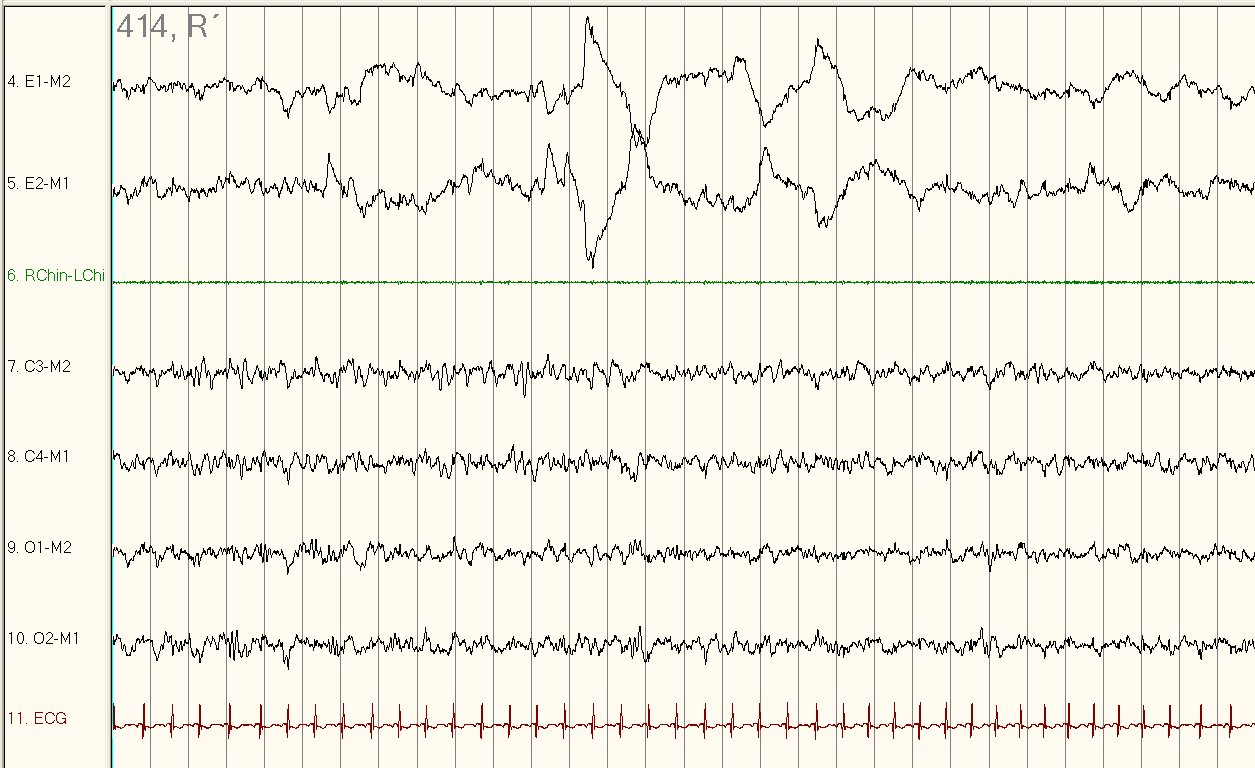

Figure 1 displays a 30-second tracing of stage N2 sleep with two rapid eye movements (red arrow) and a run of slow rolling eye movements (black arrows) on the electrooculographic (EOG) channel consistent with the use of Fluoxetine or another selective serotonin reuptake inhibitor (SSRI). Note that despite the rapid eye movements, the K complex (white arrow) seen on electroencephalogram (EEG) as well as the presence of muscle tone on chin electromyogram (EMG) indicates the eye movements are not part of stage REM sleep. As a comparison, Figure 2 provides a representative example of normal REM sleep in this patient with muscle atonia on chin EMG.